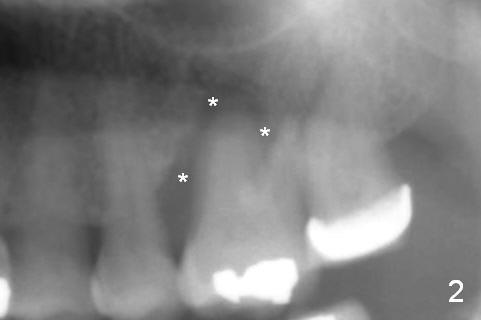

A 54-year-old woman has history of chronic periodontitis with bruxism. Bone loss at the tooth #14 starts at the mesial crest (Fig.1: 2008), extends to the mesial root (Fig.2, 2015) and the palatal one (Fig.3, 2016). The periodontal pockets are deep with mobility III. Since the defect is large with low bone density, Magic osteotomes are going to be used for CMC immediately after extraction (Clindamycin). If there is no history of sinusitis, a 11 mm long implant will be placed (Fig.4). Allograft (.5-1.5 mm) will be delivered with the large bone carrier for CMC (prior to implant placement) and the amalgam carriers for socket gap closure (before and after implant placement).